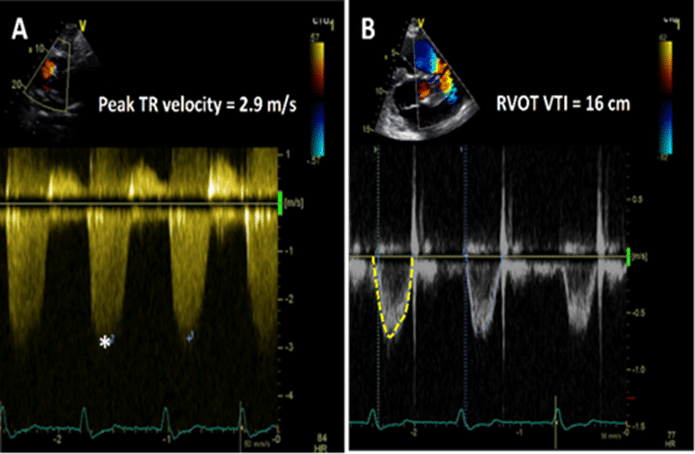

PVR can be estimated from the ratio of peak TR velocity measured with CW Doppler in meters/sec to RVOT VTI measured with PW Doppler in cm